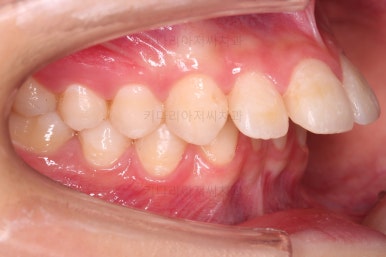

초진 시 입안의 모습입니다.

위아랫니가 많이 삐뚤진 않는데 뭔가 이상하죠?

어금니 맞물림은 지그재그로 잘 맞물려 있는데 위아래 앞니는 서로 앞뒤로 매우 멀죠.

비밀은 매우 자연스러워 보이지만 아래 앞니 2개가 선천 결손인 상태였습니다.

그래서 마치 단추 갯수와 단추구멍 갯수가 맞지 않아 단추가 남아버린 상황과 같았습니다.

앞니가 매우 튀어나와 보이고요.

당연히 앞니 기능은 못하게 됩니다.

앞니끼리 맞물리지 않다보니 아래 앞니는 점점 솟구쳐 과개교합(깊게 맞물려 아래 앞니가 거의 보이지 않는 현상)이 되게 됩니다.